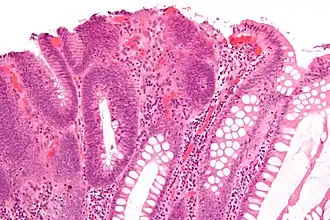

| Type | Risk of containing malignant cells | Histopathology | Image | |

| Tubular adenoma | 2% at 1.5 cm[12] | Low to high grade dysplasia[13] | Over 75% of volume has tubular appearance.[14] |

|

Adenomas

Neoplastic polyps of the bowel are often benign hence called adenomas. An adenoma is a tumor of glandular tissue, that has not (yet) gained the properties of cancer.

The common adenomas of the colon (colorectal adenoma) are the tubular, tubulovillous, villous, and sessile serrated (SSA).[18] A large majority (65–80%) are of the benign tubular type with 10–25% being tubulovillous, and villous being the most rare at 5–10%.[9]

-

Micrograph of a tubular adenoma – dysplastic epithelium (dark purple) on left of image; normal epithelium (blue) on right. H&E stain. -